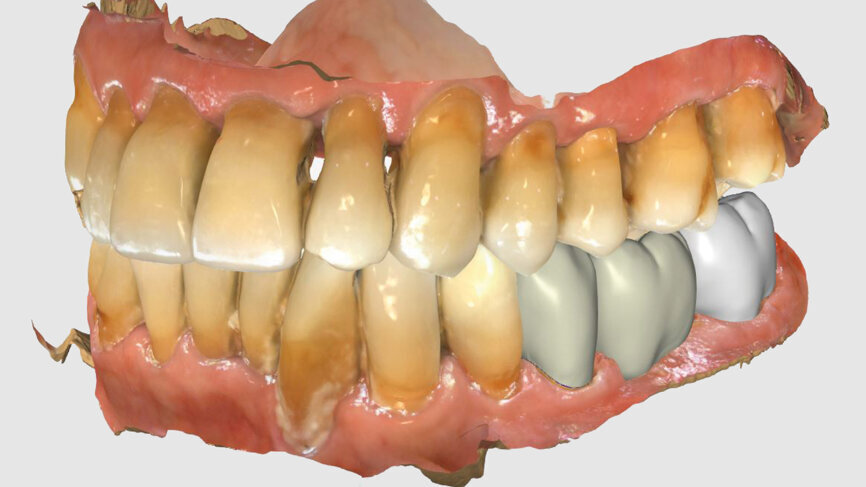

Fig. 4: Bridge design using CEREC Software.

Fig. 5: Bridge design using CEREC Software.

Fig. 6: Owing to the bright shade of the teeth in the cuspal area, the restoration was positioned high in the multilayered KATANA Zirconia Block.